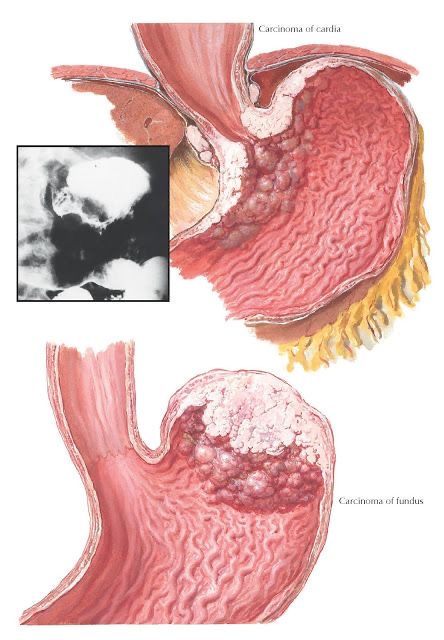

Сахипов Муса Мендыбаевич специализируется на передовых, минимально инвазивных хирургических методах лечения  ожирения, сахарного диабета и метаболического синдрома, хирургических поражений печени, желчных путей и поджелудочной железы, запущенных заболеваний органов брюшной полости, забрюшинного пространства и всего желудочно-кишечного тракта.